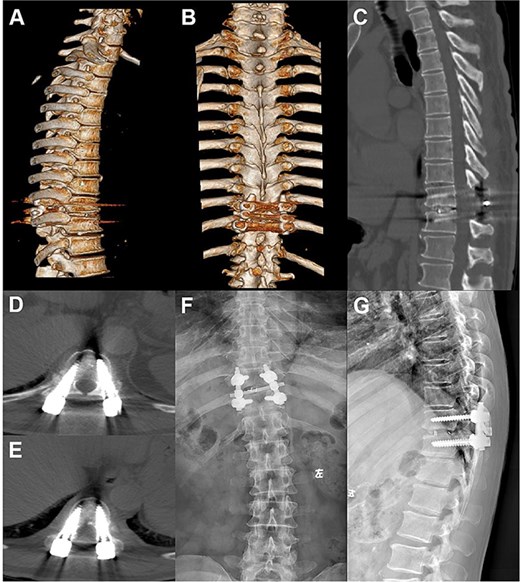

Postoperative follow-up images. (A–D) Repeat CT plain and 3D reconstruction at 6 months postoperatively showed ideal position of the T10–11 internal fixation and fusion device, straight posterior margin of the vertebral body, and no obvious signs of compression of the dural sac. (E, F) Review X-ray at 1 year postoperatively showed that the internal fixation device was in place without obvious dislocation, and the vertebral body slippage was satisfactorily repositioned.